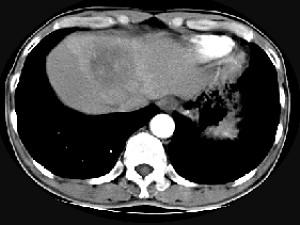

问题 男,61岁,寒战高热,右上腹痛,白细胞计数升高,CT检查如图,最可能的诊断是 ( )

选项 A、炎性肉芽肿 B、肝转移瘤 C、肝血管瘤 D、肝脓肿 E、原发性肝癌

答案 D